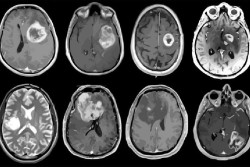

Los pacientes con cáncer de páncreas en estadio II que reciben quimioterapia seguida de una intervención para eliminar la parte cancerosa del órgano, viven casi el doble de tiempo que los pacientes que reciben quimioterapia sola, según una nueva investigación publicada en línea en el `Journal of the American College of Surgeons`.